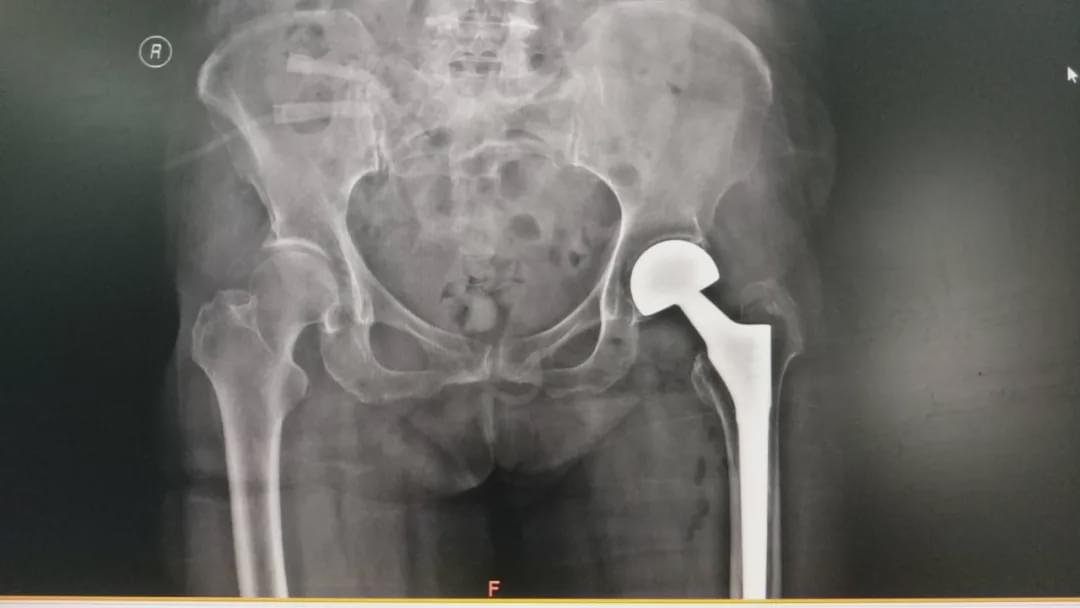

驻马店市的臧女士,今年80岁,十余年前因股骨颈骨折行左侧人工股骨头置换术。近日,不慎摔伤导致左髋部疼痛、不能活动,当时未给予检查及治疗,自行在家卧床休息,几天后,症状无缓解。9月2日被家属送到驻马店市中心医院就诊,经过接诊医生检查,诊断为“左侧人工股骨头置换术后假体松动”。随后到关节外科住院治疗。

根据病情该患者需行人工髋关节翻修术,但患者高龄,有多种内科疾病,手术创伤及难度较大。既往有10年余房颤及高血压病史,且2月前因胆囊结石进行过手术治疗,患者对于手术治疗及预后有些焦虑。

根据臧女士的病情,关节外科高山主任及主治医师李张等人共同为患者制定了周密的治疗方案,在手术部及麻醉科配合下,为她施行“左侧人工髋关节翻修术”。经过2小时的共同努力,手术顺利完成,术后患者生命体征平稳,且无任何不适,在医护人员的正确指导下,患者术后第1天抬腿、第2天下床活动,明显缩短卧床时间,经过治疗于9月12日康复出院,得到了患者及家属的感谢。(南媛媛 李沐佳)